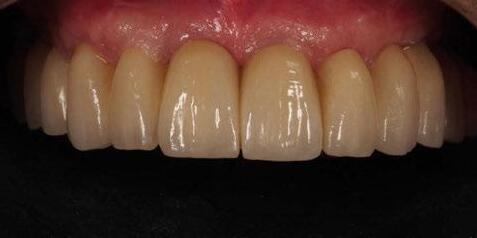

directamente a cabeza de implante para realizar una prótesis dentoalveolar de cerámica de 3 piezas, que equilibraran la oclusión y dieran soporte al labio y la mejilla (Figuras 14-17)

Figura 14. Imagen intraoral frontal postoperatoria al año de la reconstrucción.

Figura 15. Detalle de prótesis dentoalveolar cerámica en visión lateral.